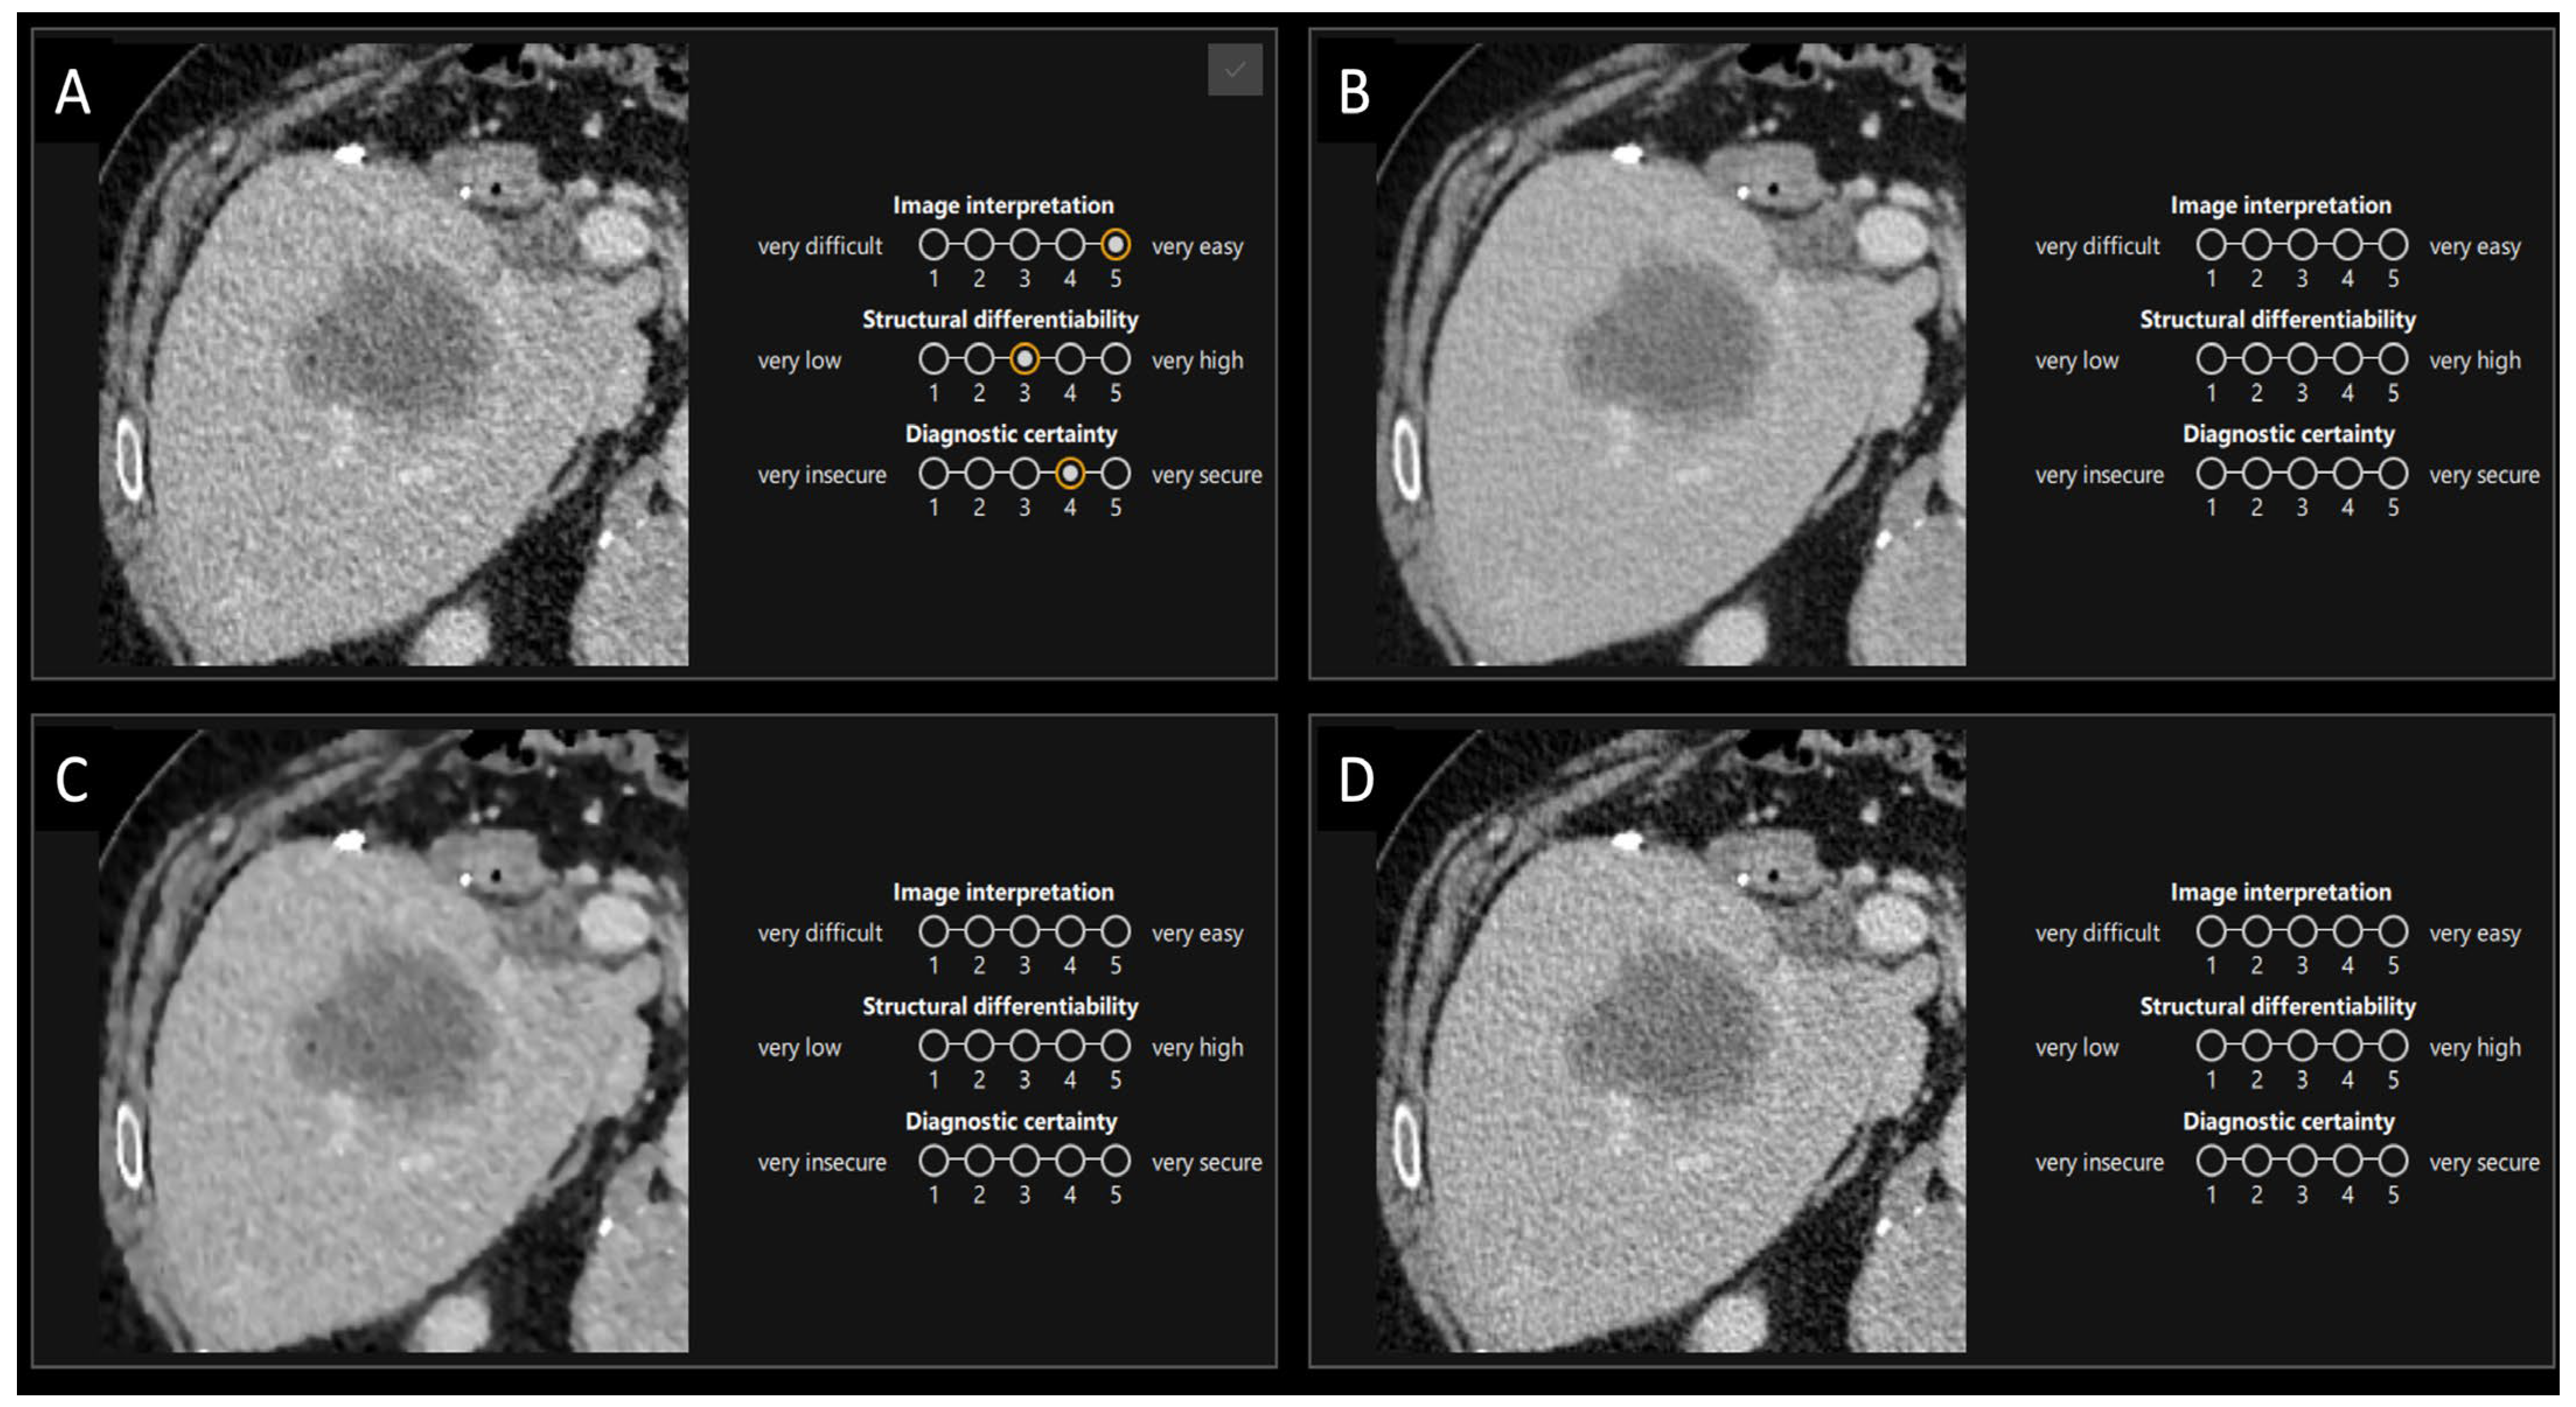

2.5.2. Second Part

| This study | 28 | 0–17 | 33 | chest, abdomen and pelvis staging | art. and pv. | - GE Revolution with stagging protocol (voltage: 120 kVp, slice thickness 0.625 mm) - Reconstructions: FBP, ASIR-V (30%, 50%, 70%, 100%), Pixelshine (Soft, Ultrasoft), DLIR (High, Medium, Low) - Evaluation: qualitative analysis of ranked image quality on a scale from 1 (best) to 8 (worst); qualitative analysis of image interpretation, structural differentiability, and diagnostic certainty for ASIR-V 50%, ASIR-V 100% DLIR-High and DLIR-Low using a 5-point Likert scale; quantitative analysis of SNR and CNR | - Qualitative: DLIR-High ranked highest, followed by DLIR-Medium and DLIR-Low; ASIR-V 50%, Pixelshine Soft, and Ultrasoft were mid-ranked, with FBP and ASIR-V 100% at the bottom; DLIR-High is preferred for all three criteria (image interpretation, diagnostic certainty, and structural differentiability), followed by DLIR-Low, ASIR-V 50%, and ASIR-V 100%. - No significant difference in evaluation between younger and older radiologists, or between arterial and portal venous phases. - Quantitative: SNR and CNR (best to worst)—DLIR-High = ASIR-V 100%, DLIR-Medium = ASIR-V 70%, DLIR-Low = PS Ultrasoft = ASIR-V 50%, PS Soft, ASIR-V 30%, FBP; DLIR-High and ASIR-V 100% showed the highest SNR- and CNR-values with the lowest noise. |